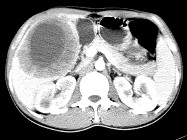

- 单项选择题女,61岁, 上腹部疼痛1个月,食欲减退, 消瘦,CT所见如图, 最可能的诊断为( )

A、原发性肝癌

B、肝包虫病

C、肝转移瘤

D、胃癌肝转移

E、肝脓肿